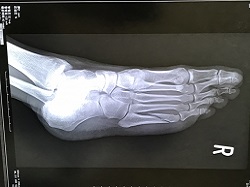

交差点で対向車と衝突してむち打ちと足の複雑骨折の診断を受け、足の骨折で2カ月入院し、その間、むち打ちの治療も行いました。

退院後も足に痛みがあったが、足の骨折の治療をした外科医は、骨折は治っているので、症状固定をして後遺障害の認定を受けるよう勧められました。